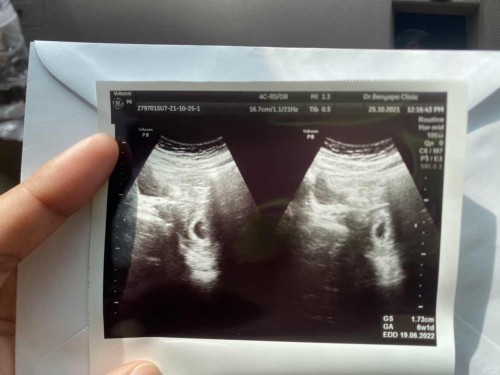

ในใบซาวด์บอกว่า 6 สัปดาห์ แต่ไม่เจอตัวอ่อน ปกติไหมคะ

ท้องแรกค่ะ ไปซาวด์ไม่เจอตัวอ่อน 6 วีค กะว่ารออีก 2-3 สัปดาห์ไปใหม่ แต่ปกติไหมคะ#ท้องแรกคะ #ขอบคุณล่วงหน้านะคะ

เดี๋ยวก็เจอค่ะอย่าพึ่งเชื่อหมอหากไม่มีเด็กจริงๆร่างกายเราจะขับออกมาเอง รอให้ถึงที่สุดก่อนค่ะ บ้านนี้ทีแรกน่าจะ7wไม่เจอแต่เหมือนจะมีใข่แดงเลี้ยงเด็กอยู่รอพอไปรอบหลัง8-9wเจอตัวค่ะ หัวใจเต้นดี ซาวด์ทีแรกตามภาพเรยค่ะตอนนี้30w+3แล้ว